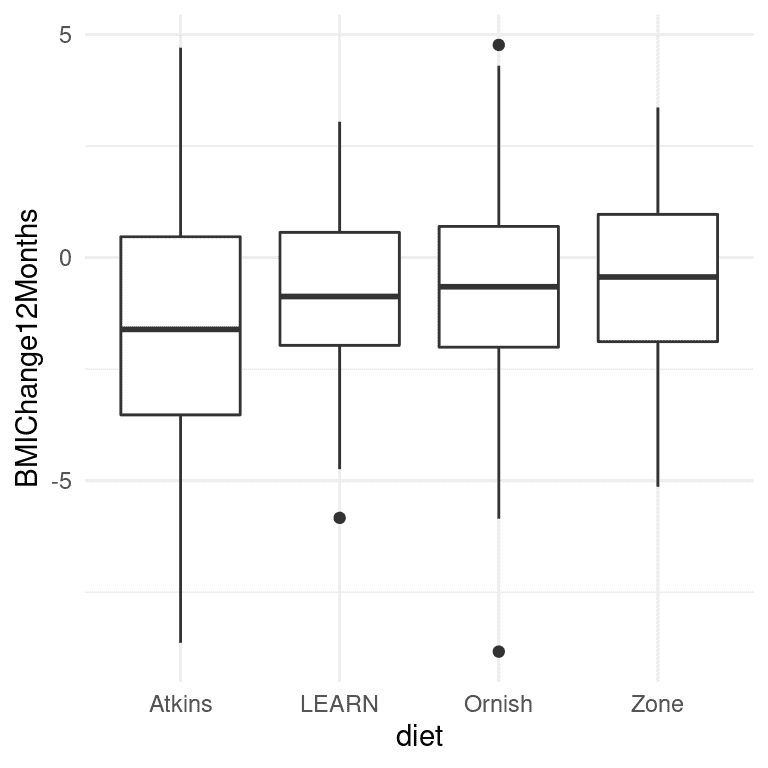

图 17.1:每个条件的箱线图,每组的第 50 百分位数(即中位数)显示为黑线。

A 到 Z 研究的实际数据并不是公开的,因此我们将使用他们的论文中报告的摘要数据来生成一些大致符合其研究中获得的数据的合成数据,每组的均值和标准差相同。 一旦我们有了数据,我们可以将它们可视化,以确保没有异常值。 箱线图对于查看分布的形状很有用,如图 17.1 所示。 这些数据看起来相当合理-在各个组内有一些异常值(由箱线图外的点表示),但它们似乎不会在其他组方面极端。 我们还可以看到,这些分布在方差上似乎有些不同,阿特金斯的变异性略大于其他饮食。 这意味着任何假设方差在各组之间相等的分析可能是不合适的。 幸运的是,我们计划使用的 ANOVA 模型对此相当健壮。

请注意,软件自动生成了对应于四种饮食中三种的虚拟变量,使得阿特金斯饮食没有虚拟变量。这意味着截距代表了阿特金斯饮食组的均值,其他三个变量则模拟了这些饮食的均值与阿特金斯饮食均值之间的差异。阿特金斯饮食被选择为未建模的基线变量,仅仅是因为它在字母顺序中排在第一位。

首先让我们回顾一下上面第 5 步中 ANOVA 的结果摘要。显著的 F 检验告诉我们饮食之间存在显著差异,但我们还应该注意到模型实际上并没有解释数据的很多变异;R 平方值只有 0.03,表明模型只解释了体重减轻变异的几个百分点。因此,我们不希望过分解释这个结果。

在整体 F 检验中的显著结果也没有告诉我们哪些饮食与其他饮食有差异。我们可以通过比较不同条件下的均值来了解更多信息。因为我们进行了几次比较,所以需要对这些比较进行校正,这是通过一种称为 Tukey 方法的程序来实现的,该方法由我们的统计软件实现:

右侧列中的字母告诉我们哪些组彼此不同,使用一种调整进行比较的方法;共享一个字母的条件彼此之间没有显著差异。这表明 Atkins 和 LEARN 饮食彼此没有差异(因为它们共享字母 a),LEARN、Ornish 和 Zone 饮食彼此没有差异(因为它们共享字母 b),但 Atkins 饮食与 Ornish 和 Zone 饮食有差异(因为它们没有共享字母)。